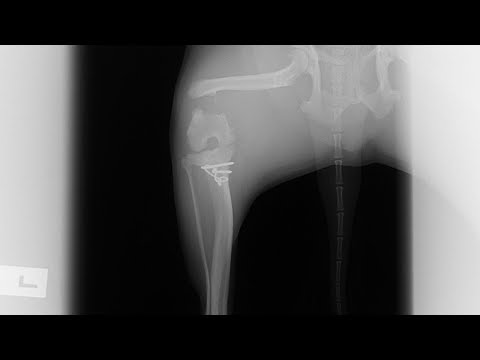

Перелом бедра у собаки

Перелом бедра у собаки 113 фотографий